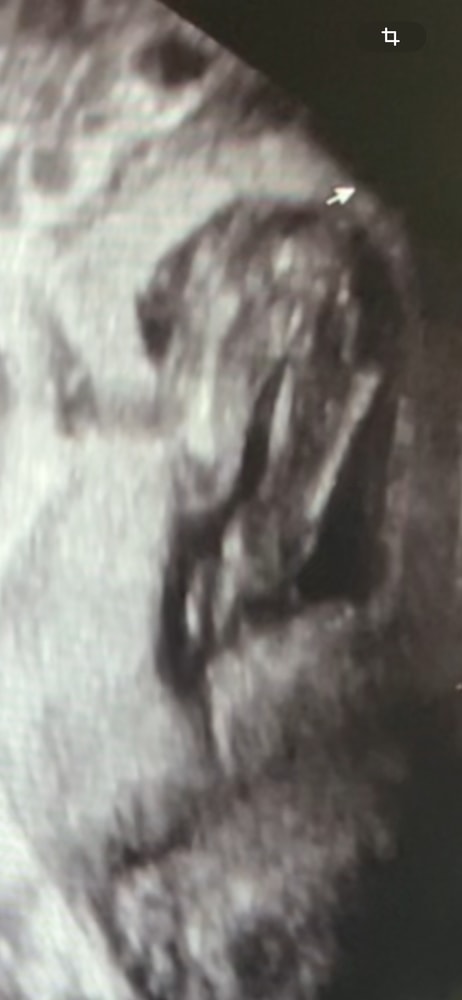

УЗИ

Видны половые губы

Да, девчонка) Вижу кофейное зернышко, как у дочки) У мальчиков хорошо пипка видна с этого ракурса

Как мать трех девочек, тщательно разглядывавшая все узи на этих сроках, тоже вижу девочку)))

УЗИ 5+3 24 дпп ровно 6недель